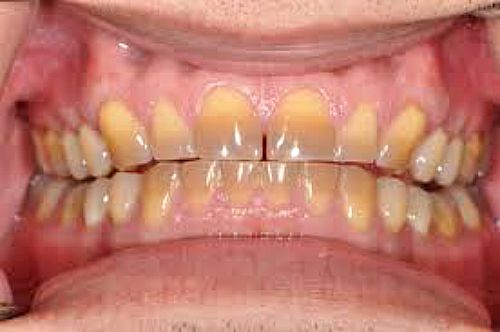

Dental staining can be a real problem in today's esthetic world. Sometimes it is extrinsic, as in coffee stains, or staining from smoking. This can be polished off.  Other times, it is intrinsic, as in tetracycline-stained teeth. When this is the case, there are only three solutions: bleaching, veneers or full crowns.